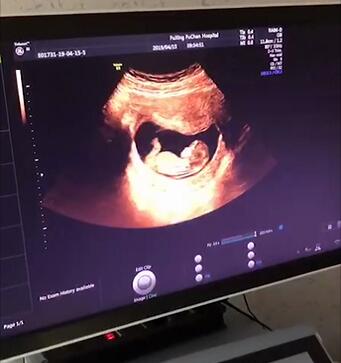

NT检查

是早孕期产前筛查的重要项目

能筛查出异常可能性较高的胎儿畸形

是不可错过的第一次产前筛查

NT检查有严格的时间要求

为孕11周—13周+6天

筛查唐氏儿、先心病,优生优育必要检查

NT检查是筛查胎儿有没有先天愚型,是优生优育必要的检查。颈项透明层越厚,胎儿异常的概率越大,意味着胎宝宝可能存在以下问题:

检查时间要求“苛刻”,孕11-13w+6过时不候

做NT检查的最佳时间是孕11-13w+6天,此时头臀长相当于45-84mm。

NT的变化与孕周密切相关,规定测量其厚度的时间也很严格。颈后透明带扫描选在孕11~13周+6天进行,原因是过了14周,过多的液体可能被胎儿正在发育的淋巴系统吸收,检查结果就会不准确。